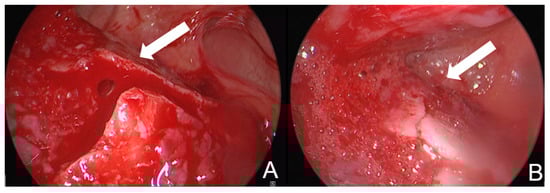

A 2.7 mm 30° endoscope is inserted through the bony window to access the frontal sinus. This allows for direct visualization of the fracture prior to reduction. The fracture is then reduced using a small, rigid instrument such as an LPRF plugger or urethral dilator. Following reduction, the outcome is assessed both endoscopically and by manual palpation (Figure 2). If possible, a perioperative CBCT was taken to verify the reduction in the frontal sinus. In other cases, if no CBCT could be taken perioperatively, a control CT scan was made within 1 week after the procedure.

Figure 2. (A) Image of the fracture of the anterior wall of the frontal sinus before reduction; (B) image of the fracture of the anterior wall after reduction in the same patient. The anterior wall of the sinus is located at the bottom of the image. The fracture line is indicated with an arrow in both images.